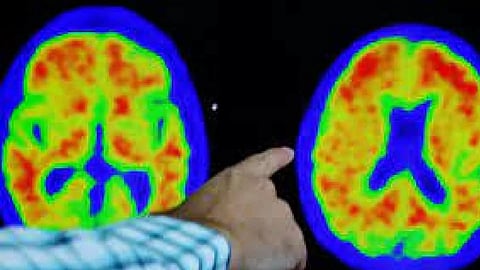

Researchers then pivoted to a safer route, infusing highly targeted man-made antibodies into patients that sidestep the body's immune machinery. Eisai and Biogen's newly launched Leqembi and Eli Lilly's donanemab, now under U.S. regulatory review, are two such treatments that cemented the view that removing amyloid is key to fighting Alzheimer's in people with early-stage disease. That success followed years of failures that left many experts questioning the amyloid theory.

The first Alzheimer's vaccine demonstrated signs of benefit, but also triggered an out-of-control response from the immune system's T-cells, which are only supposed to destroy infected cells. Most of the newer vaccines target B cells, immune cells that produce antibodies.